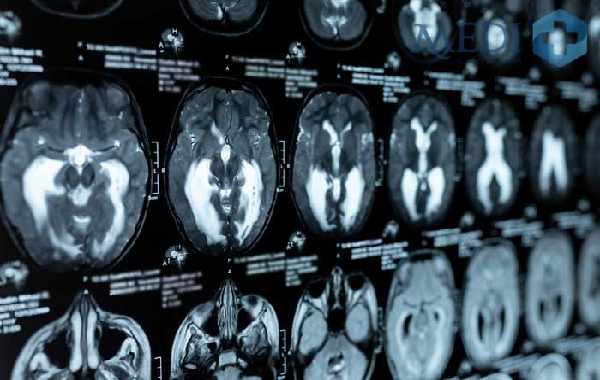

Chụp cộng hưởng từ (MRI) giúp phát hiện các vấn đề bất thường đặc biệt là khối u giai đoạn sớm, nâng cao hiệu quả điều trị bệnh.

Kỹ thuật chụp cộng hưởng từ (MRI) sử dụng từ trường và sóng radio để tạo hình cắt lớp bộ phận trên cơ thể con người. Có hàng triệu nguyên tử hydro trong cơ thể, chúng sẽ hấp thụ và giải phóng năng lượng sóng từ trường dưới dạng tín hiệu khi chụp cộng hưởng từ (MRI).

Sau đó các tín hiệu này sẽ truyền về máy ghi nhận và cho ra kết quả dưới dạng hình ảnh. Hình ảnh này thể hiện cấu trúc cơ thể rõ nét và độ phân giải cao. Các kết quả này cũng có thể được bác sĩ tái tạo 3D để tăng hiệu quả chẩn đoán và thăm khám bệnh nhân.

- Chụp cộng hưởng từ (MRI) giúp chẩn đoán bệnh hiệu quả: Chụp cộng hưởng từ (MRI) cho ra ảnh chụp có độ tương phản cao, cấu trúc giải phẫu chi tiết và có thể được bác sĩ tái tạo ở dạng hình ảnh 3D. Đặc biệt, người bệnh khi chụp cộng hưởng từ (MRI) mạch máu không cần tiêm thuốc tương phản mà vẫn cho ra kết quả ổn định. Ngoài ra, những tổn thương, vấn đề bất thường, các khối u trên cơ thể (kể cả khối u có kích thước nhỏ hơn 3mm) vẫn có thể được phát hiện khi thực hiện chụp cộng hưởng từ (MRI)